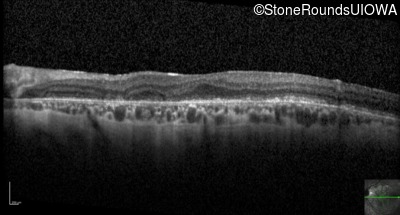

Optical Coherence Tomography - Right - 20/100 +1

Exemplar / OCT Stack